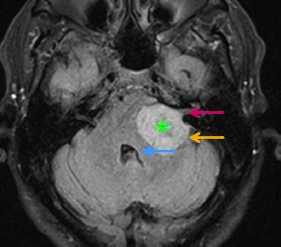

Типичные опухоли этой области невриномы (шванномы) и менингиомы. При невриномах может быть фрагмент опухоли во внутреннем слуховом проходе, что видно, особенно при МРТ головного мозга с контрастированием.

МРТ головного мозга. Т1-зависимая МРТ с контрастированием. Шваннома со сдавлением 4 желудочка.

МРТ головного мозга. Шваннома с компонентом внутри канальца.

Вестибулокохлеарный нерв (VIII) состоит из 4 пучков. Опухоли происходят обычно из вестибулярной его части. Шваннома - инкапсулированная доброкачественная (градация 1) опухоль, происходящая из дифференцированных неопластических шванновских клеток оболочек периферических нервов. Невриномы ММУ составляют около 3% опухолей головного мозга. Часть шванном (двухсторонние слуховых нервов) связана с НФ 2 типа. Пик частоты между 40 и 60 годами. Растут медленно и крайне редко малигнизируются. Клинические проявления связаны с нарушением функции нерва и компрессией ствола. Шваннома может происходить из любого отрезка по ходу нерва и хорошо прослеживается при МРТ области ММУ. Невринома видна как на Т2-взвешенных, так и на Т1-взвешенных МРТ в виде округлого образования. Невриномы хорошо и равномерно усиливаются после МРТ с введением контрастного вещества. Невриномы области цистерны могут иметь компонент во внутреннем слуховом проходе, особенно, хорошо видимый при МРТ головного мозга с контрастированием. Изредка встречаются невриномы полностью расположенные внутри канальца. Они составляют наибольшую диагностическую сложность при МРТ, требуют тонких срезов и контрастирования. Менингиомы ММУ обычно типично расположены и при МРТ имеют характерную форму и типичные черты при МРТ с контрастированием. Однако редко встречаются внутриканальцевые менингиомы. При МРТ они неотличимы от неврином. Холестеатомы при МРТ имеют смешанную интенсивность сигнала, в зависимости от их содержимого. На диффузионно-взвешенных МРТ холестеатомы обычно яркие.